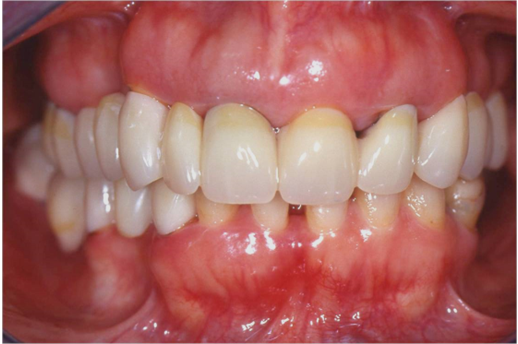

Ασθενής ετών 50 προσήλθε στο ιατρείο με κύρια ενόχληση την αιμορραγία των ούλων και τη μετακίνηση των δοντιών. Οι περιοδοντικοί ιστοί ήταν ρόδινοι και εντοπισμένα ερυθροί, ενώ οι μεσοδόντιες θηλές διογκωμένες. Πολλά δόντια εμφάνιζαν υφιζήσεις, ενώ χαρακτηριστική ήταν η υπερέκφυση και απόκλιση του πλαγίου τομέα άνω αριστερά.

Παράλληλα με την περιοδοντική θεραπεία έγινε η αφαίρεση των παλαιών προσθετικών εργασιών και τοποθέτηση νέων μεταβατικών (προσωρινών) αποκαταστάσεων. Μετά τη μη χειρουργική θεραπεία παρατηρείται απουσία φλεγμονής.

ΑΡΧΙΚΗ ΚΛΙΝΙΚΗ ΕΙΚΟΝΑ

ΤΕΛΙΚΗ ΚΑΤΑΣΤΑΣΗ